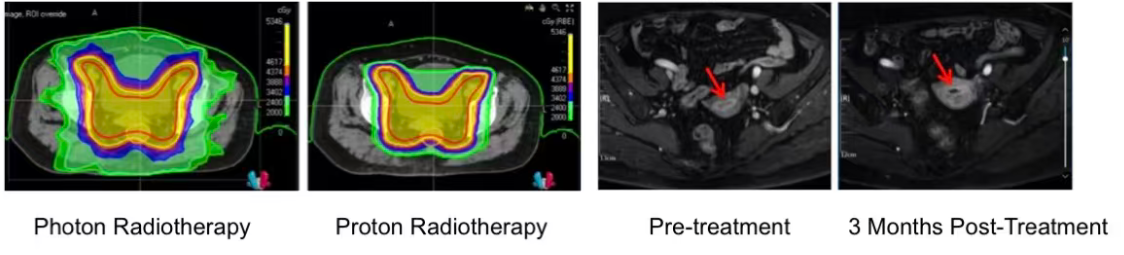

Kỹ thuật IMRT tiên tiến: Hệ thống máy xạ trị điều khiển biến phổ giúp phân bổ năng lượng phóng xạ tập trung tối đa vào khối u tái phát, đồng thời tạo ra các “vùng đệm” bảo vệ tuyệt đối cho khung sống, thân não và dây thần kinh thị giác giác.

Khối u tiêu chuẩn phổ biến: Hình ảnh CT đối chiếu cho khối u tái sinh phát hiện ở vòng cung đã thu nhỏ và gần như biến mất hoàn toàn. Các triệu chứng khó chịu như đau nhức, nhức mũi hay ù tai của bệnh nhân được cải thiện hoàn thiện.